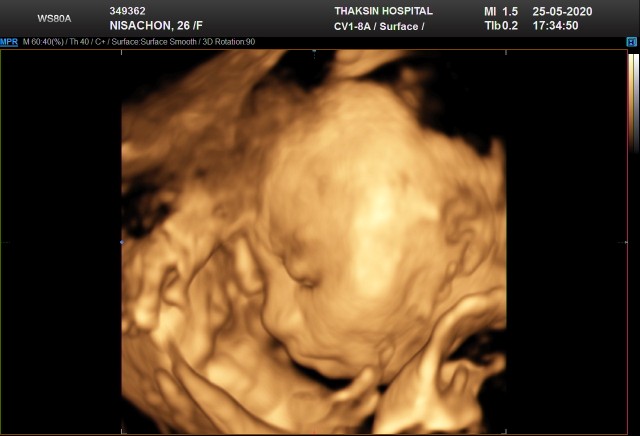

บ้านนี้ 31w ละคะ กำหนดคลอด 6 สิงหา น้อง ผญ #พึ่งไปซาว4มิติมา #เห้นน้องชัดมากอิแม่ปลื้ม ?